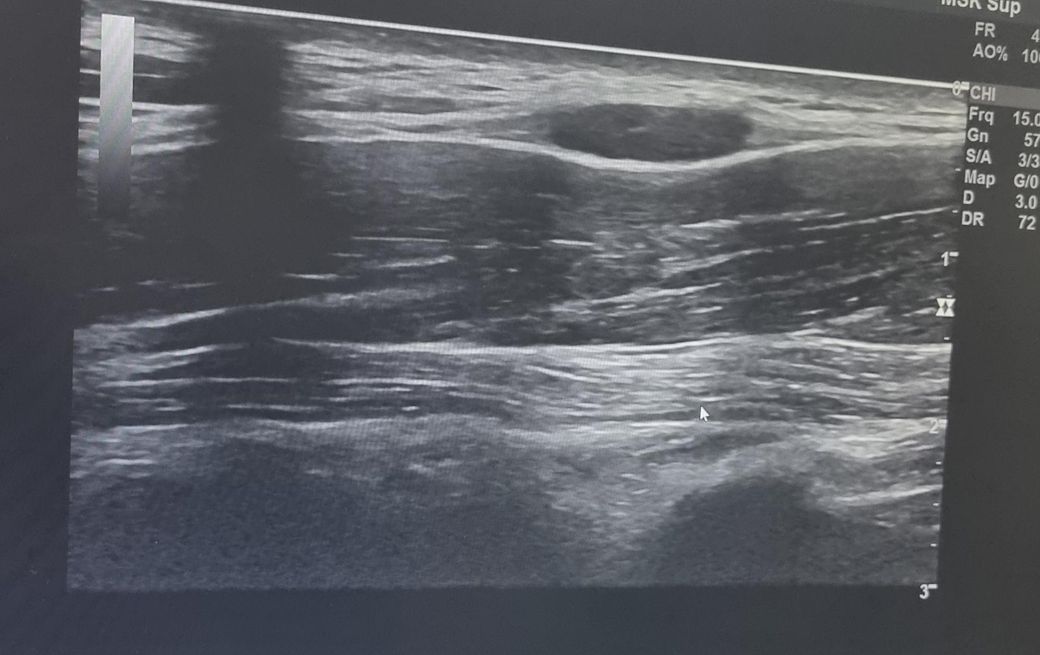

한 달 넘게 멍울 만져져서 초음파 받았는데 크기가 좀 커서요 괜찮나요? 궁금합니다 ㅜㅜ V5 구역입니다.

초음파 사진 괜찮나요 ㅜㅜ?